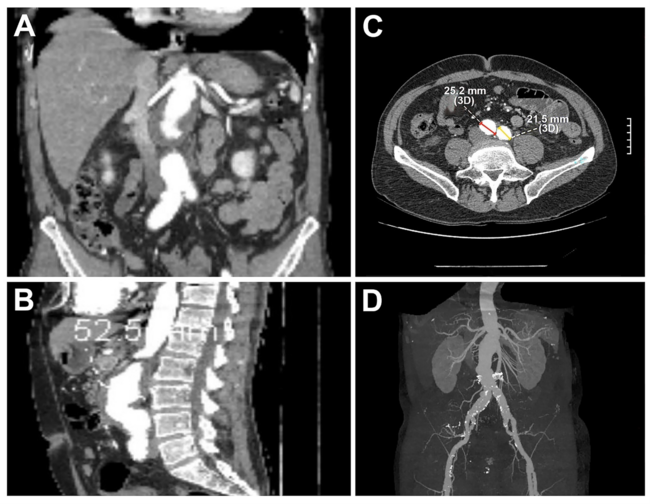

Endovascular Repair of a Complex Thoracoabdominal Aneurysm Using Thoracoabdominal Branch Endoprosthesis (TAMBE) in a High-Risk Vascular Patient

Video 1. Intraoperative angiography following deployment of the Thoracoabdominal Branch Endoprosthesis (TAMBE) device (W. L. Gore & Associates, Inc.). Post-catheterization angiogram showed successful deployment of the TAMBE.